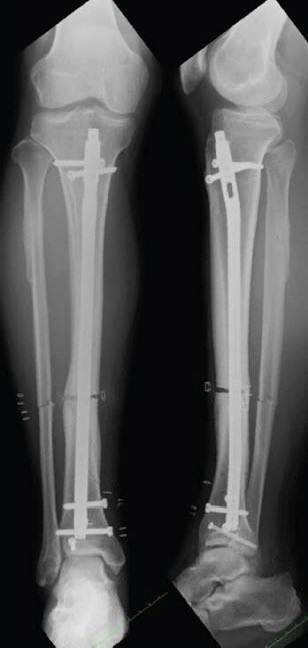

🟧 fuck guns https://t.co/qvDfgjlDMZ https://t.co/CA9zM2kXw8